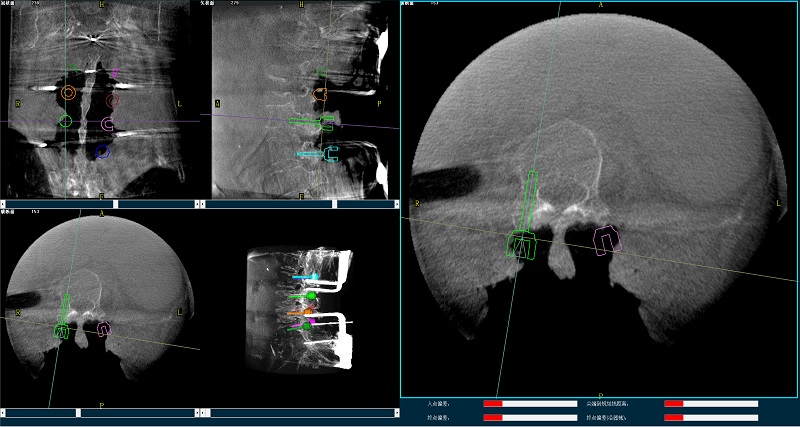

機(jī)器人輔助腰椎后路側(cè)彎矯形手術(shù)三維圖像

三維圖像

(2)使用普愛醫(yī)療平板三維C形臂掃描患者,得到術(shù)中三維圖像并傳送至骨科機(jī)器人導(dǎo)航系統(tǒng)。骨科機(jī)器人導(dǎo)航系統(tǒng)基于高清術(shù)中三維圖像進(jìn)行手術(shù)規(guī)劃。